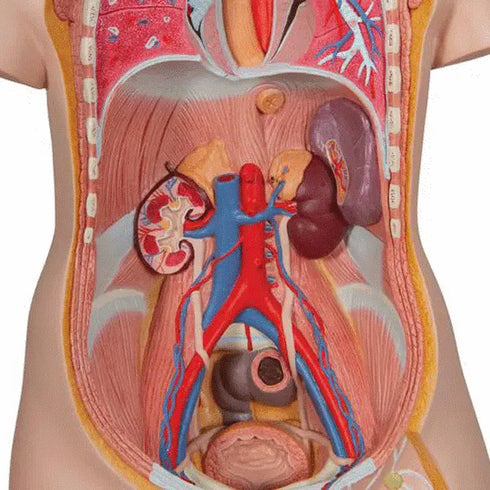

Urmatoarele componente ale acestui tors unisex sunt detasabile:

- jumatatea din fata a rinichiului;

- jumatatea din fata a vezicii urinare.